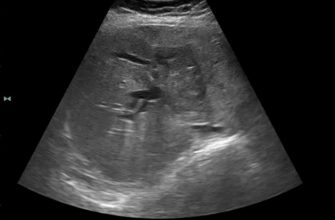

Ультразвуковое исследование — это безболезненный и высокоинформативный метод, позволяющий получить визуальную картину состояния железы.

Наиболее распространённый вариант — трансректальное УЗИ, при котором датчик вводится в прямую кишку. Такой подход помогает точно определить размер, структуру и наличие опухолей или симметричных изменений в простате.